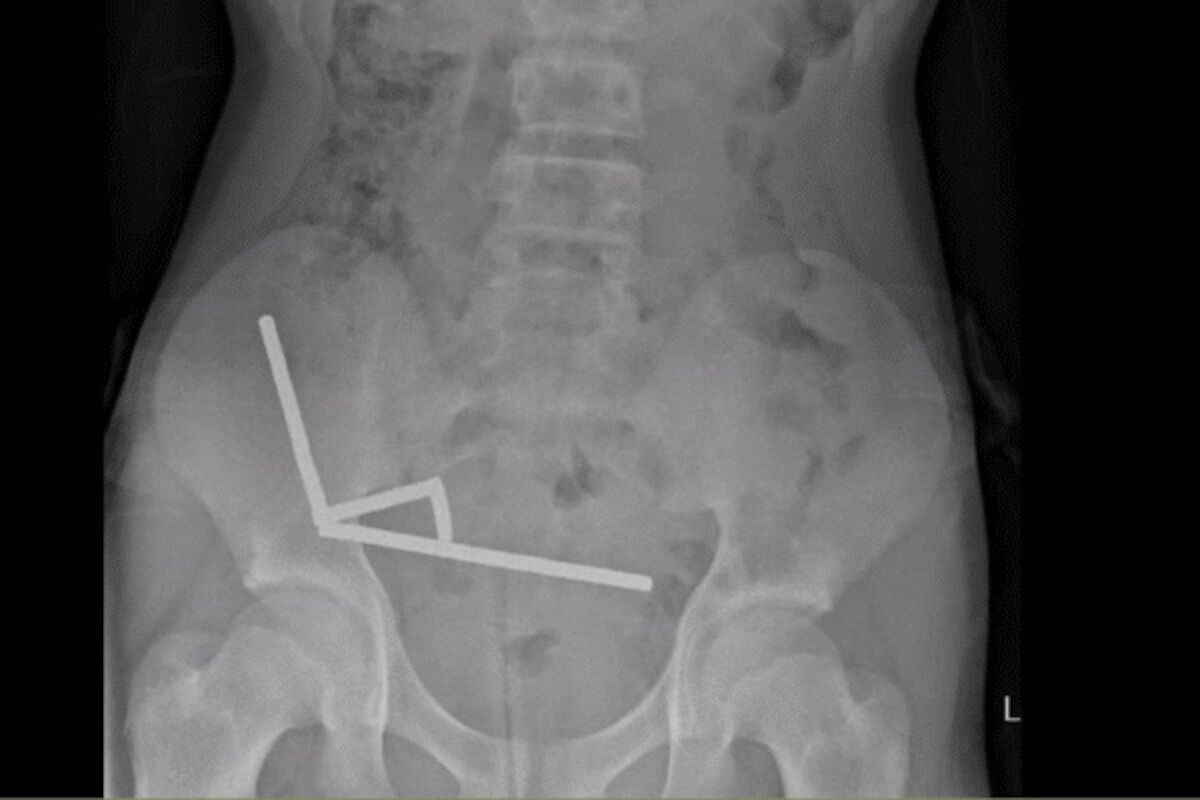

X-ray showing magnetic currents in the New Zealand teenager’s abdomen.

A 13-year-old boy in New Zealand had part of his intestine surgically removed after ingesting almost 200 high-powered magnets.

Once inside the abdomen, the small metallic objects came together, as the report describes, in a destructive way. By compressing, they were causing several areas of tissue to die due to lack of blood, in a phenomenon known as pressure necrosis.